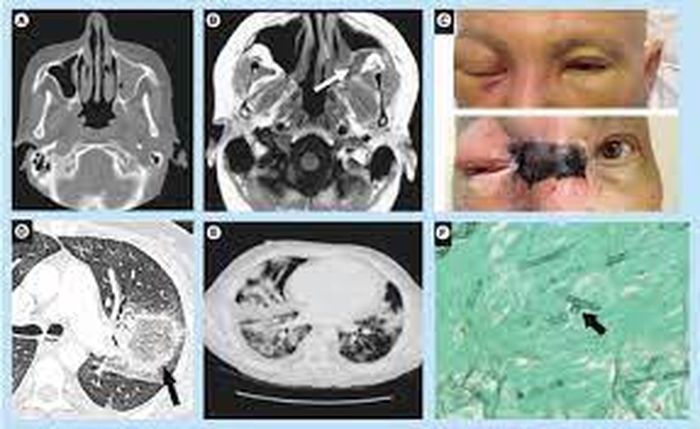

INFEKSI Jamur Hitam Di India Buat Bola Mata Pasien Covid-19 Harus

jamur kini diangkat pasien infeksi

hitam jamur serang infeksi pasien matanya komorbid meninggal diangkat mucormycosis